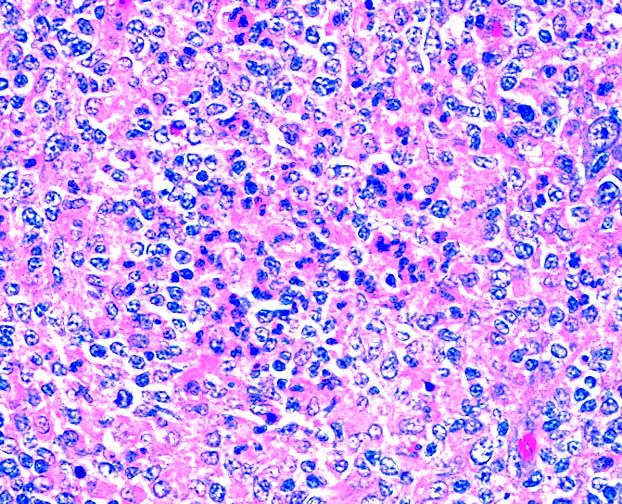

Microscopic (histologic) description

- Nodes show partial / complete effacement by storiform pattern of bland spindle cells, some with vacuoles

- Numerous vessels lined by plump endothelial cells, plasma cells and lymphocytes

Microscopic (histologic) images

Contributed by AFIP and Chunyu Cai, M.D., Ph.D. (Case #532)